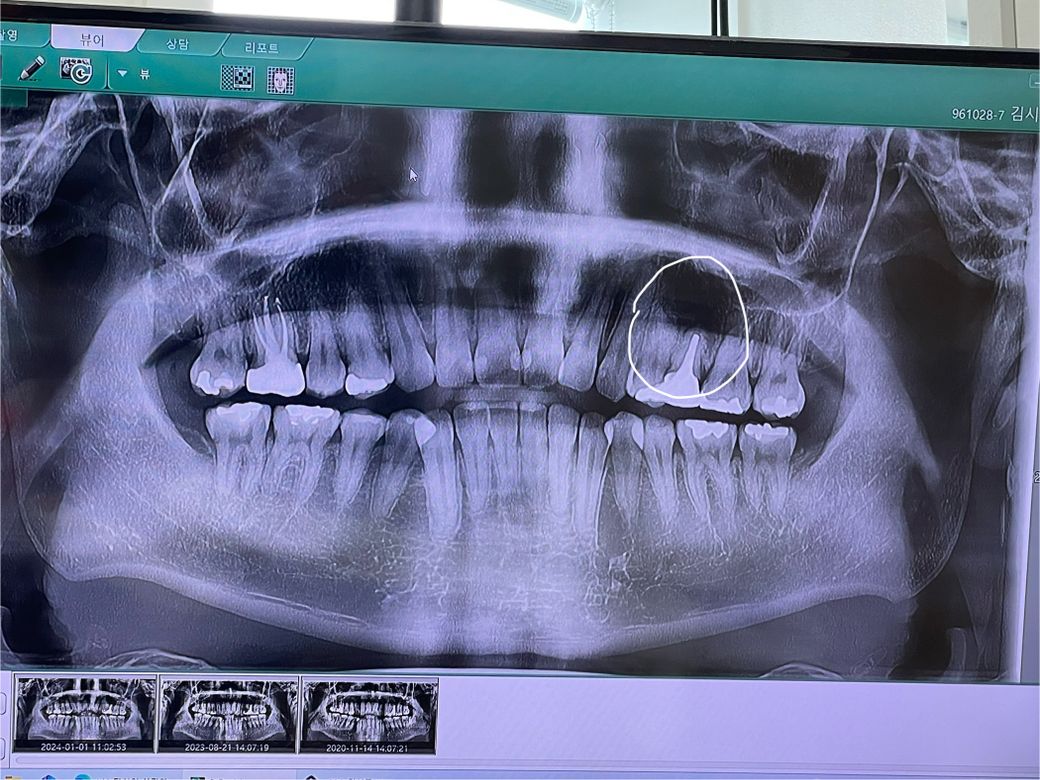

옛날에 치아에 포스트를 세우고 크라운을 씌운 치아가 크라운 씌운지 오래돼서 교체를 하였습니다 지르코니아로 포스트 기둥은 그대로 두고 크라운만 교체를 하였는데 크라운 교체할 때 망치 같은 걸로 뽑고 교체 르루 했는데 그 이후부터 잇몸이랑 주변 부위에 통증이 너무 심합니다 그래서 치과를 방문하니 치아 뿌리 쪽에 염증이 생겼다고 했는데 교체하기가 충격으로 인해 생긴 건가요? 그래서 어떻게 해야 하나 여쭤보니 여기서 손을 더 대면 임플란트를 할 수 있으니 그대로 두 자고 하시더라고요 근데 제가 치아 뿌리 염증에 대해서 찾아보니 치근 단 절제술도 있고 잇몸을 열어서 염증을 긁어내는 치료방법도 있던데 왜 안 해주시고 그냥 쓰라고 하시는 건지 궁급합니다 그리고 무조건 임플란트밖에 방법이 없다고 하셔서 정말 그런 건가요 그대로 두고 더 써보자고 하시는데 점점 염증도 커지고 나중에는 더 심해져서 위에 치근단 치료 같은 것도 못 받는 게 아닌지 궁급합니다 통증도 점점 심해지고 주변 치아까지 망가지는 게 아닌지 걱정됩니다 어떤 치료를 받아야 할까요 사진 첨부합니다

• 3번 째 사진

포스트 치료가 돼 있는 경우에는 근관 치료가 어려운 경우가 많습니다. 재신경 치료가 가능하다면 재신경 치료를 받는 것이 좋으며 제 신경 치료를 받기 힘들거나 치아뿌리에 금이 갔을 경우에는 발치를 해야 할 경우도 생기게 됩니다. 자세한 확인을 위해 치과에서 진료를 받아보는 것을 권유드립니다

• 안녕하세요 치과의사 김철진입니다. 교체할때 충격으로 치아에 염증이 생기거나 그렇진 않습니다. 기존에 치료를 한부위에 염즈잉 처음부터 잇엇다면 크라운 교체 전에 미리 고지를 햇어야되지 않을까 싶습니다. 파노라마 사진보다는 작은 엑스레이 사진을 한번더 찍어보셔야될것같습니다 .